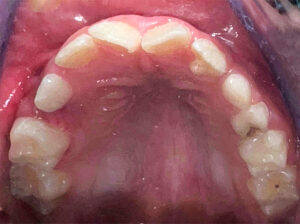

Paciente masculino de 7 años de edad acude a consulta odontológica, el cual al momento de su inspección clínica se percibe que presenta una anomalía dental en la pieza 22 (incisivo lateral superior izquierdo), la cual es identificada como talón cuspídeo de tipo 2 (semitalón), en este caso se describe como una proyección de forma cónica desde el tercio cervical del cíngulo no tan prominente hacia el borde incisal (Figura 2-3).